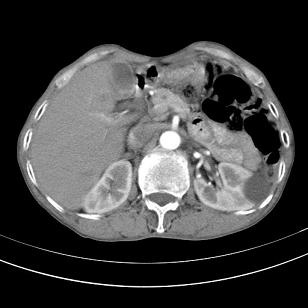

标题: 男,65岁,反复右上腹痛, [打印本页]

标题: 男,65岁,反复右上腹痛,

胃镜提示十二指肠占位